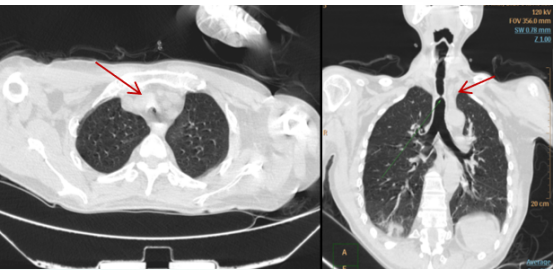

病例4:肺泡蛋白沉积症合并严重低氧血

患者女性,53岁,因“间断气短半年,加重10天”入院。胸部CT提示双肺弥漫片状磨玻璃影,边缘模糊(图9)。支气管镜病理确诊肺泡蛋白沉积症,血气分析结果:pH 7.39,PaO2 31 mmHg,PaCO2 51 mmHg,BE -4.8 mmol/L。

图片

9  患者治疗前胸部CT